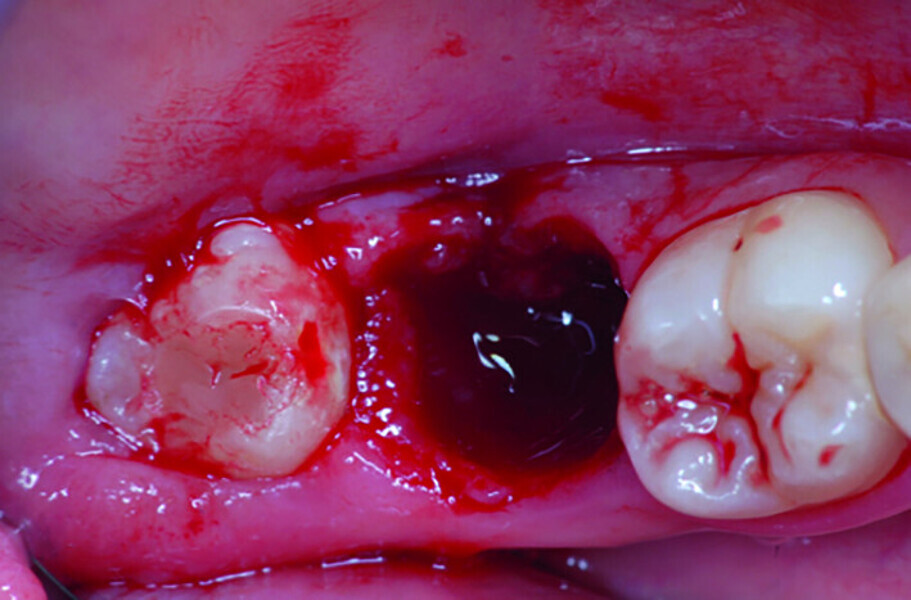

Fig. 12: Pulp chamber floor perforation, immediately after extraction.